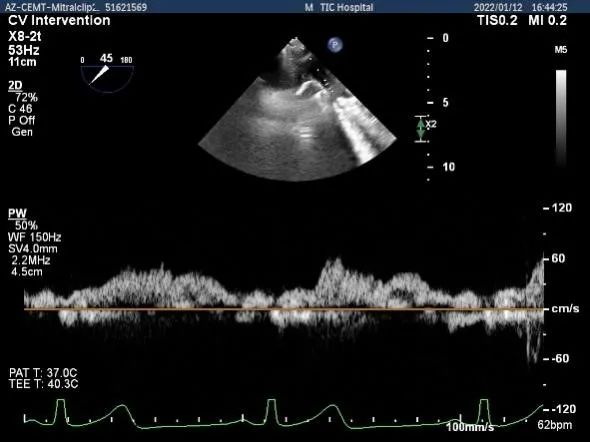

肺静脉血流频谱逐渐恢复正向

肺静脉血流频谱完全恢复正向